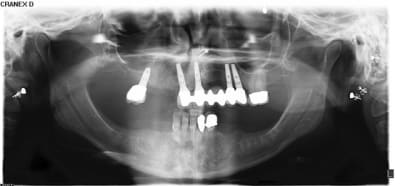

Patiente adressée pour évaluation :

son dentiste ne sait que faire.

À l'examen :

13 : belle fistule vestibulaire, mobilité, carie cervicale

14 : mobilité +++

15 : fracture racine (?), carie cervicale

Les implants datent de 5-6 ans (par un autre CD, la patiente a depuis déménagée).

Le bas , pas touche cette année, on verra en 2012.

Votre plan de tx ?

Panorex avec Vitallium en bouche ok... au moins on sait que la patiente possède un partiel...